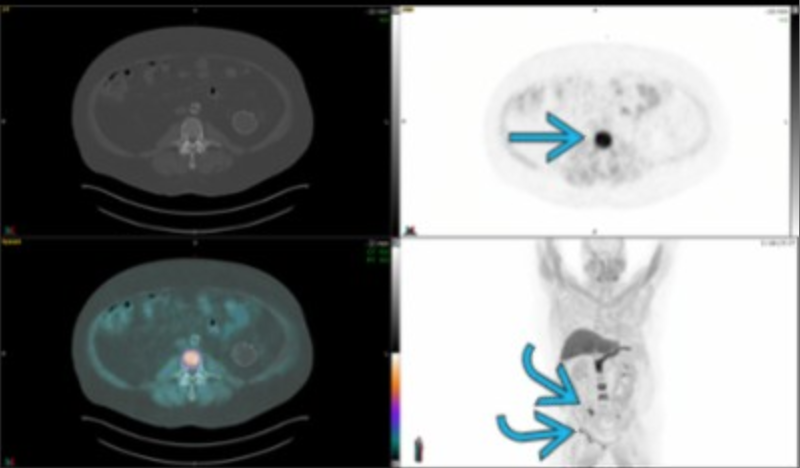

Carcinomatosis

Ga 68-Dotatate PET

Spine and pelvic mets